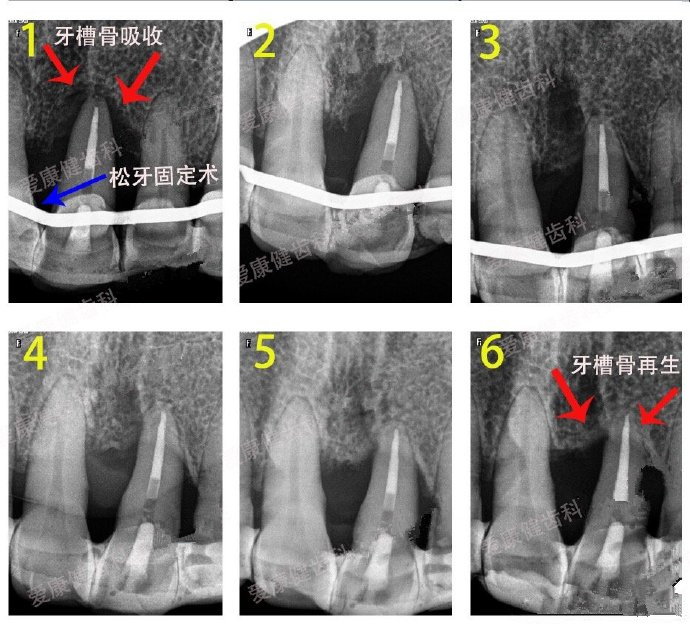

愛康健牙周醫生**:61歲**,牙齒三度鬆動麵臨(lin) 拔除,醫生建議牙周基礎治療+牙周固定,經過長期治療,挽回了這顆鬆動牙。

牙齒掉了好幾顆了,說明牙周炎已經比較嚴(yan) 重了,多半屬於(yu) 重度牙周炎了(隻是猜測,具體(ti) 需要醫生根據牙齒情況確定),通常這時候需要及時找個(ge) 專(zhuan) 業(ye) 的牙周醫生檢查和診療,確定係統的牙周治療方案,采用牙周基礎治療、牙周鬆動固定術等來盡量保留剩下的牙齒。

當然,具體(ti) 能不能保留下來,不僅(jin) 需要看牙齒鬆動程度,牙周醫生治療技術,還需要**積極配合才行。尤其是注意保持口腔清潔:每天飯後漱口刷牙、使用牙線、定期到醫院複診。真牙能保留總比的拔牙做假牙好,所以不管嚴(yan) 重牙周炎治療結果好不好,總要先試試,盡力而為(wei) 後才知道。